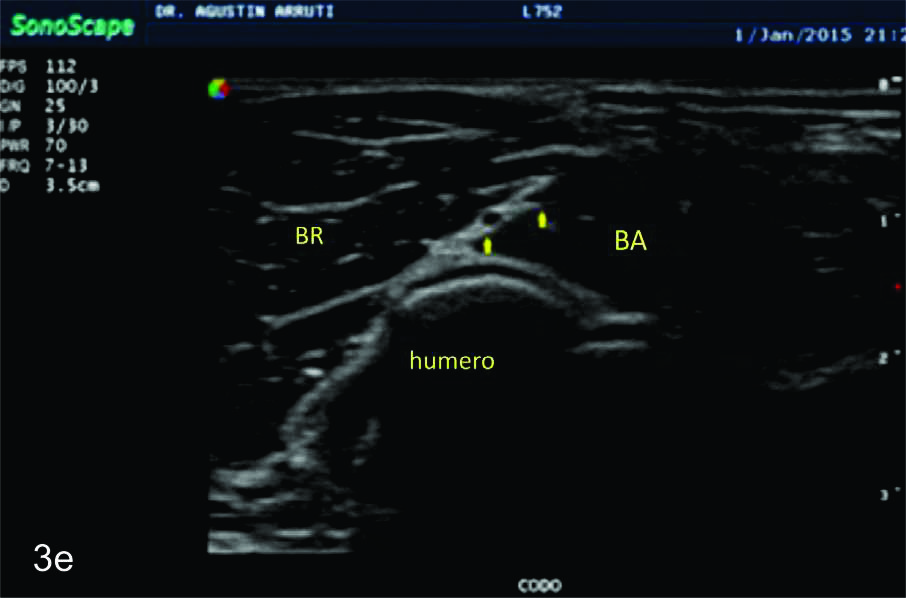

Figura 3

Nervio radial

Serie de cortes axiales del nervio radial desde su origen a nivel del hueco axilar hasta su bifurcación en sus dos ramas terminales a nivel del codo. Se identifica el mismo señalado por flechas amarillas y con las letras NR. AH-arteria humeral, tríceps- músculo tríceps, BA- músculo braquial anterior, CB- músculo coraco braquial, BR- músculo braquiorradial. A- axila, B- tercio proximal del brazo, C- tercio medio del brazo, D- tercio distal del brazo, E- codo, las flechas señalan las dos ramas terminales del nervio radial.